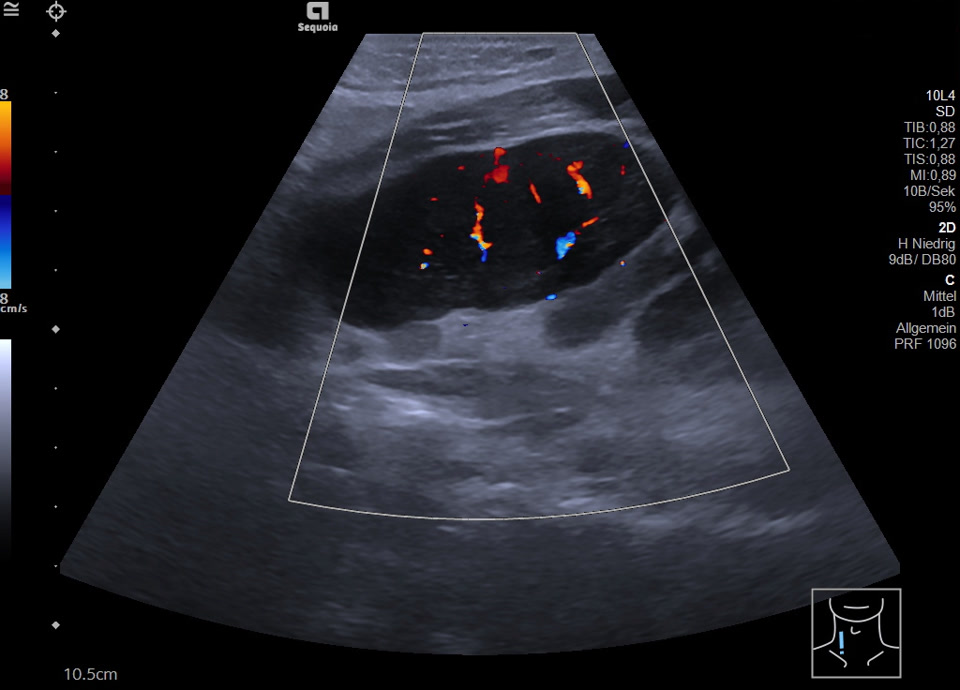

Vergrößerte retroperitoneale Lymphknoten bei Non-Hodgkin Lymphom, die sich vom Oberbauch bis in die rechte Leiste verfolgen lassen (hochfrequenter Linearschallkopf)